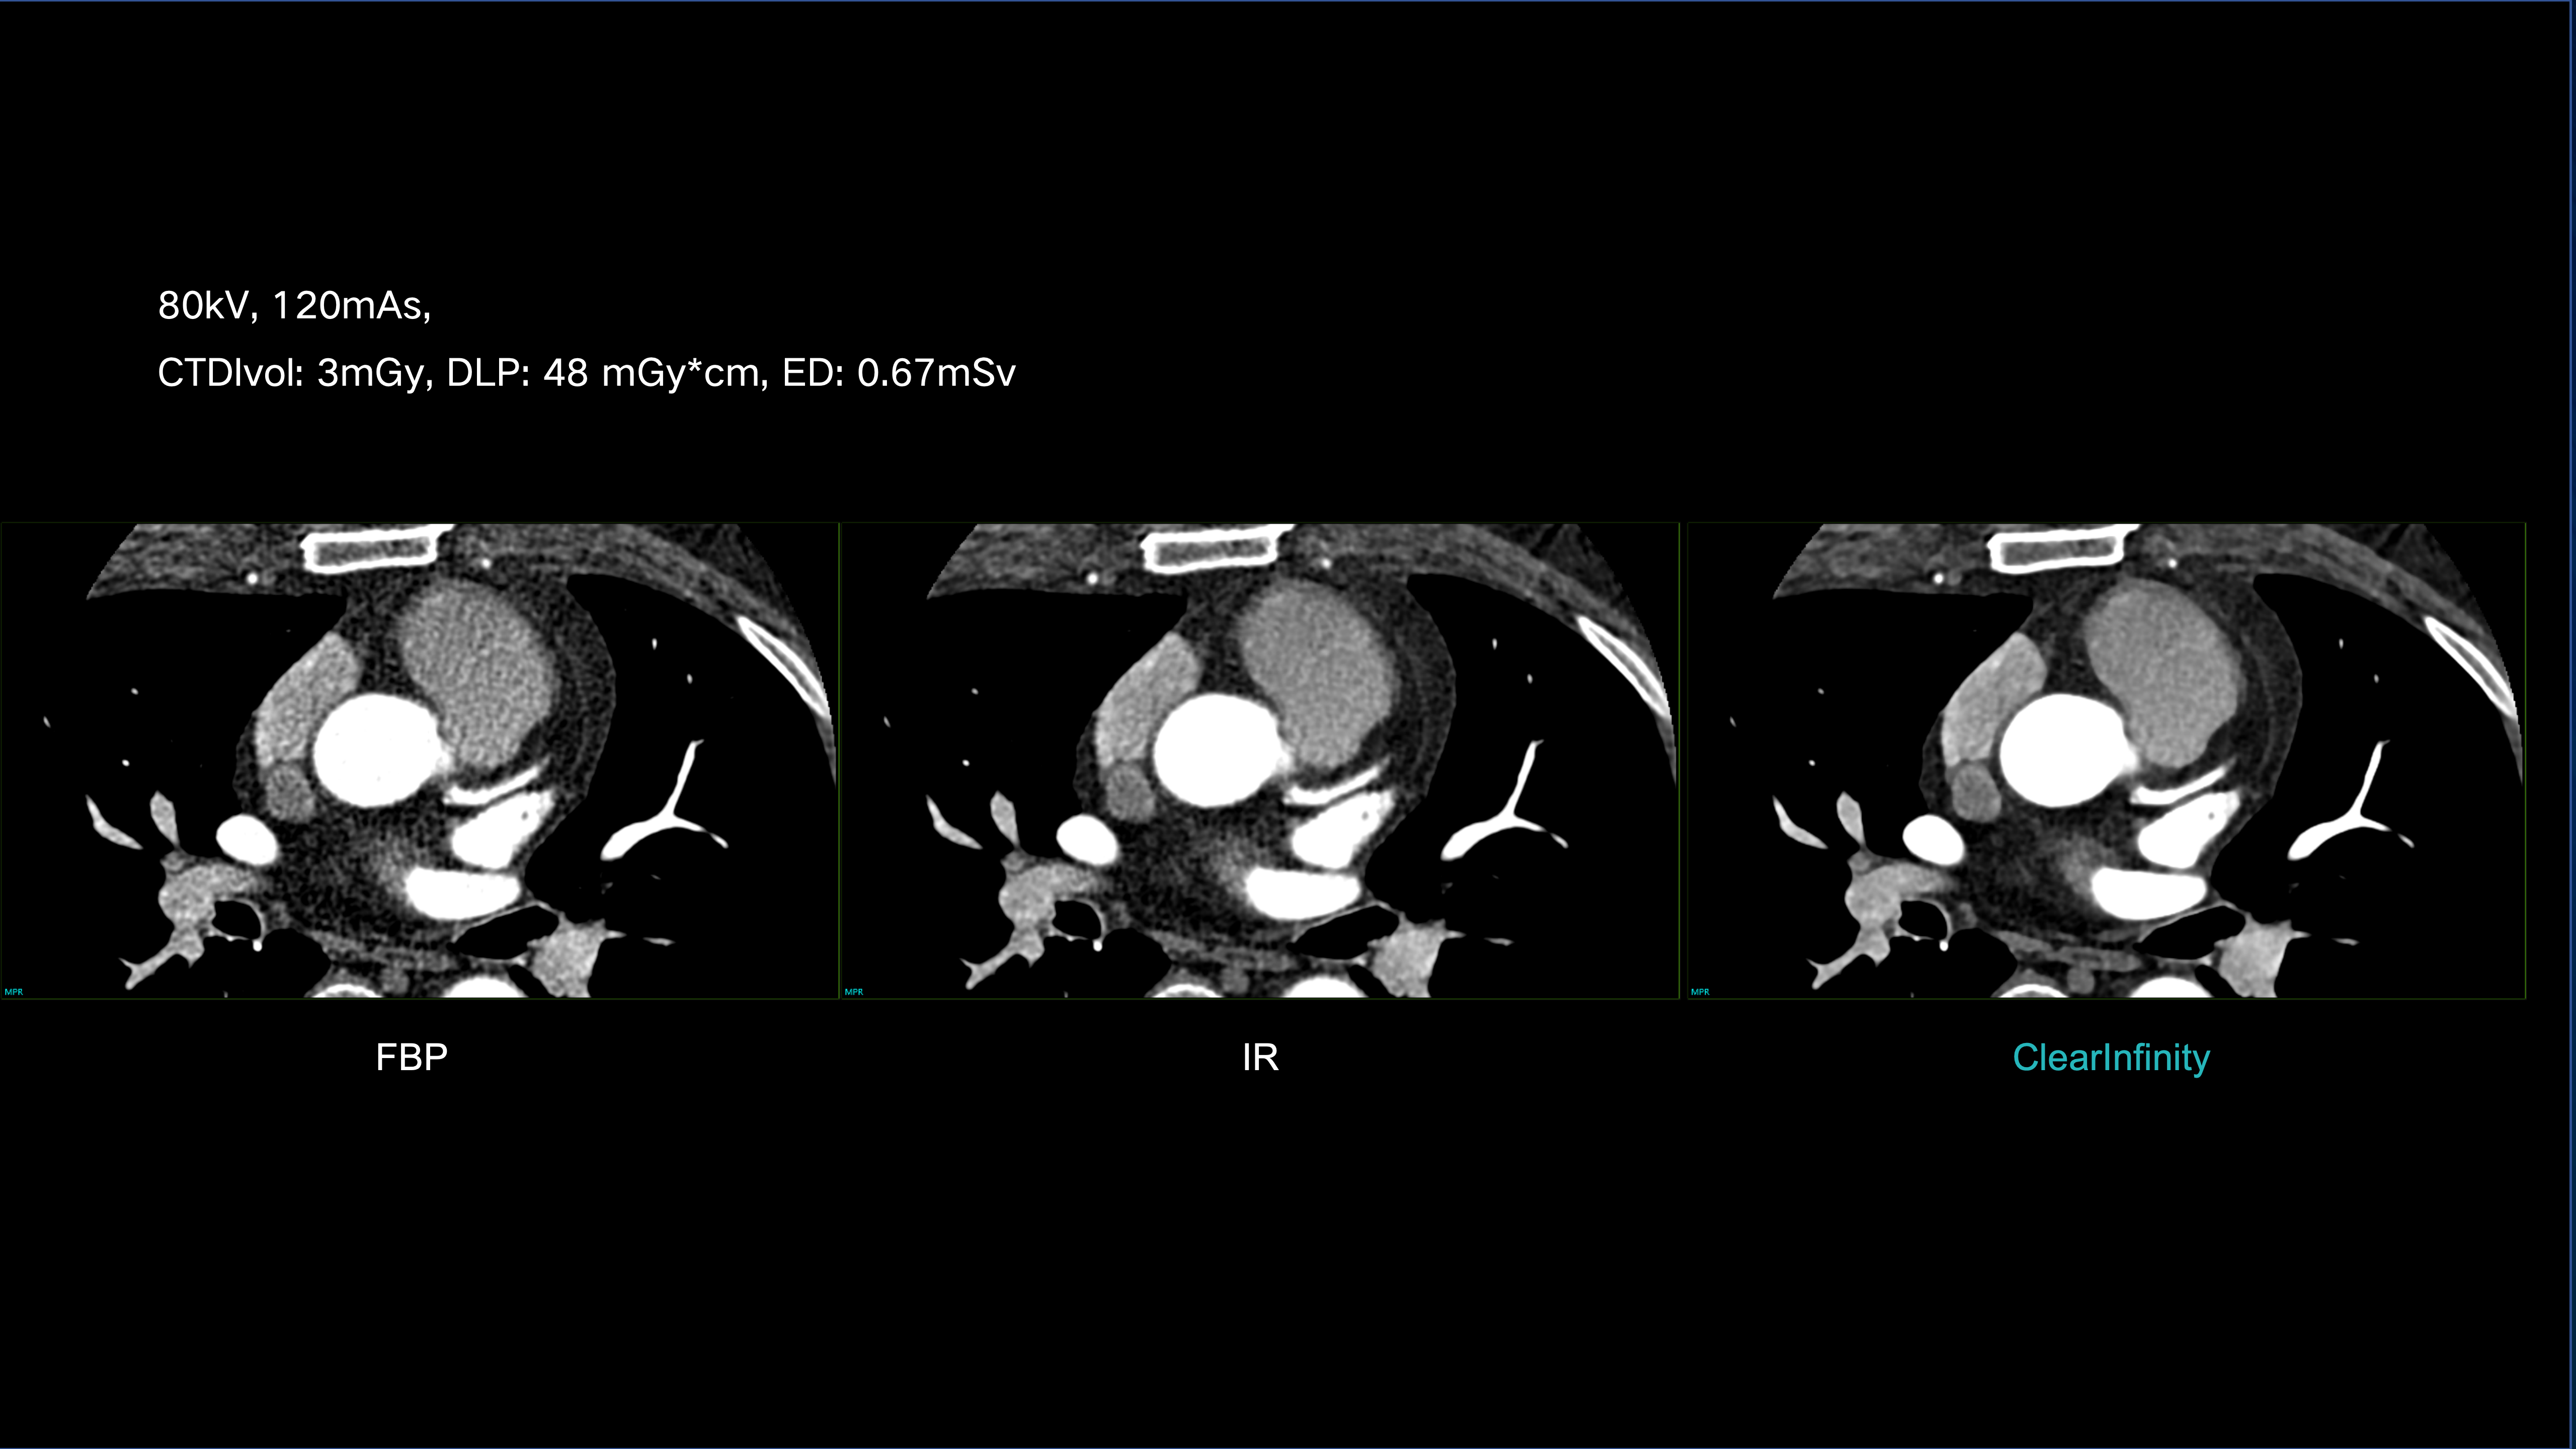

ClearInfinity AI preserves natural texture while ensuring ultra-low-dose clarity.

Delivers extraordinary spatial detail for confident, accurate diagnosis.